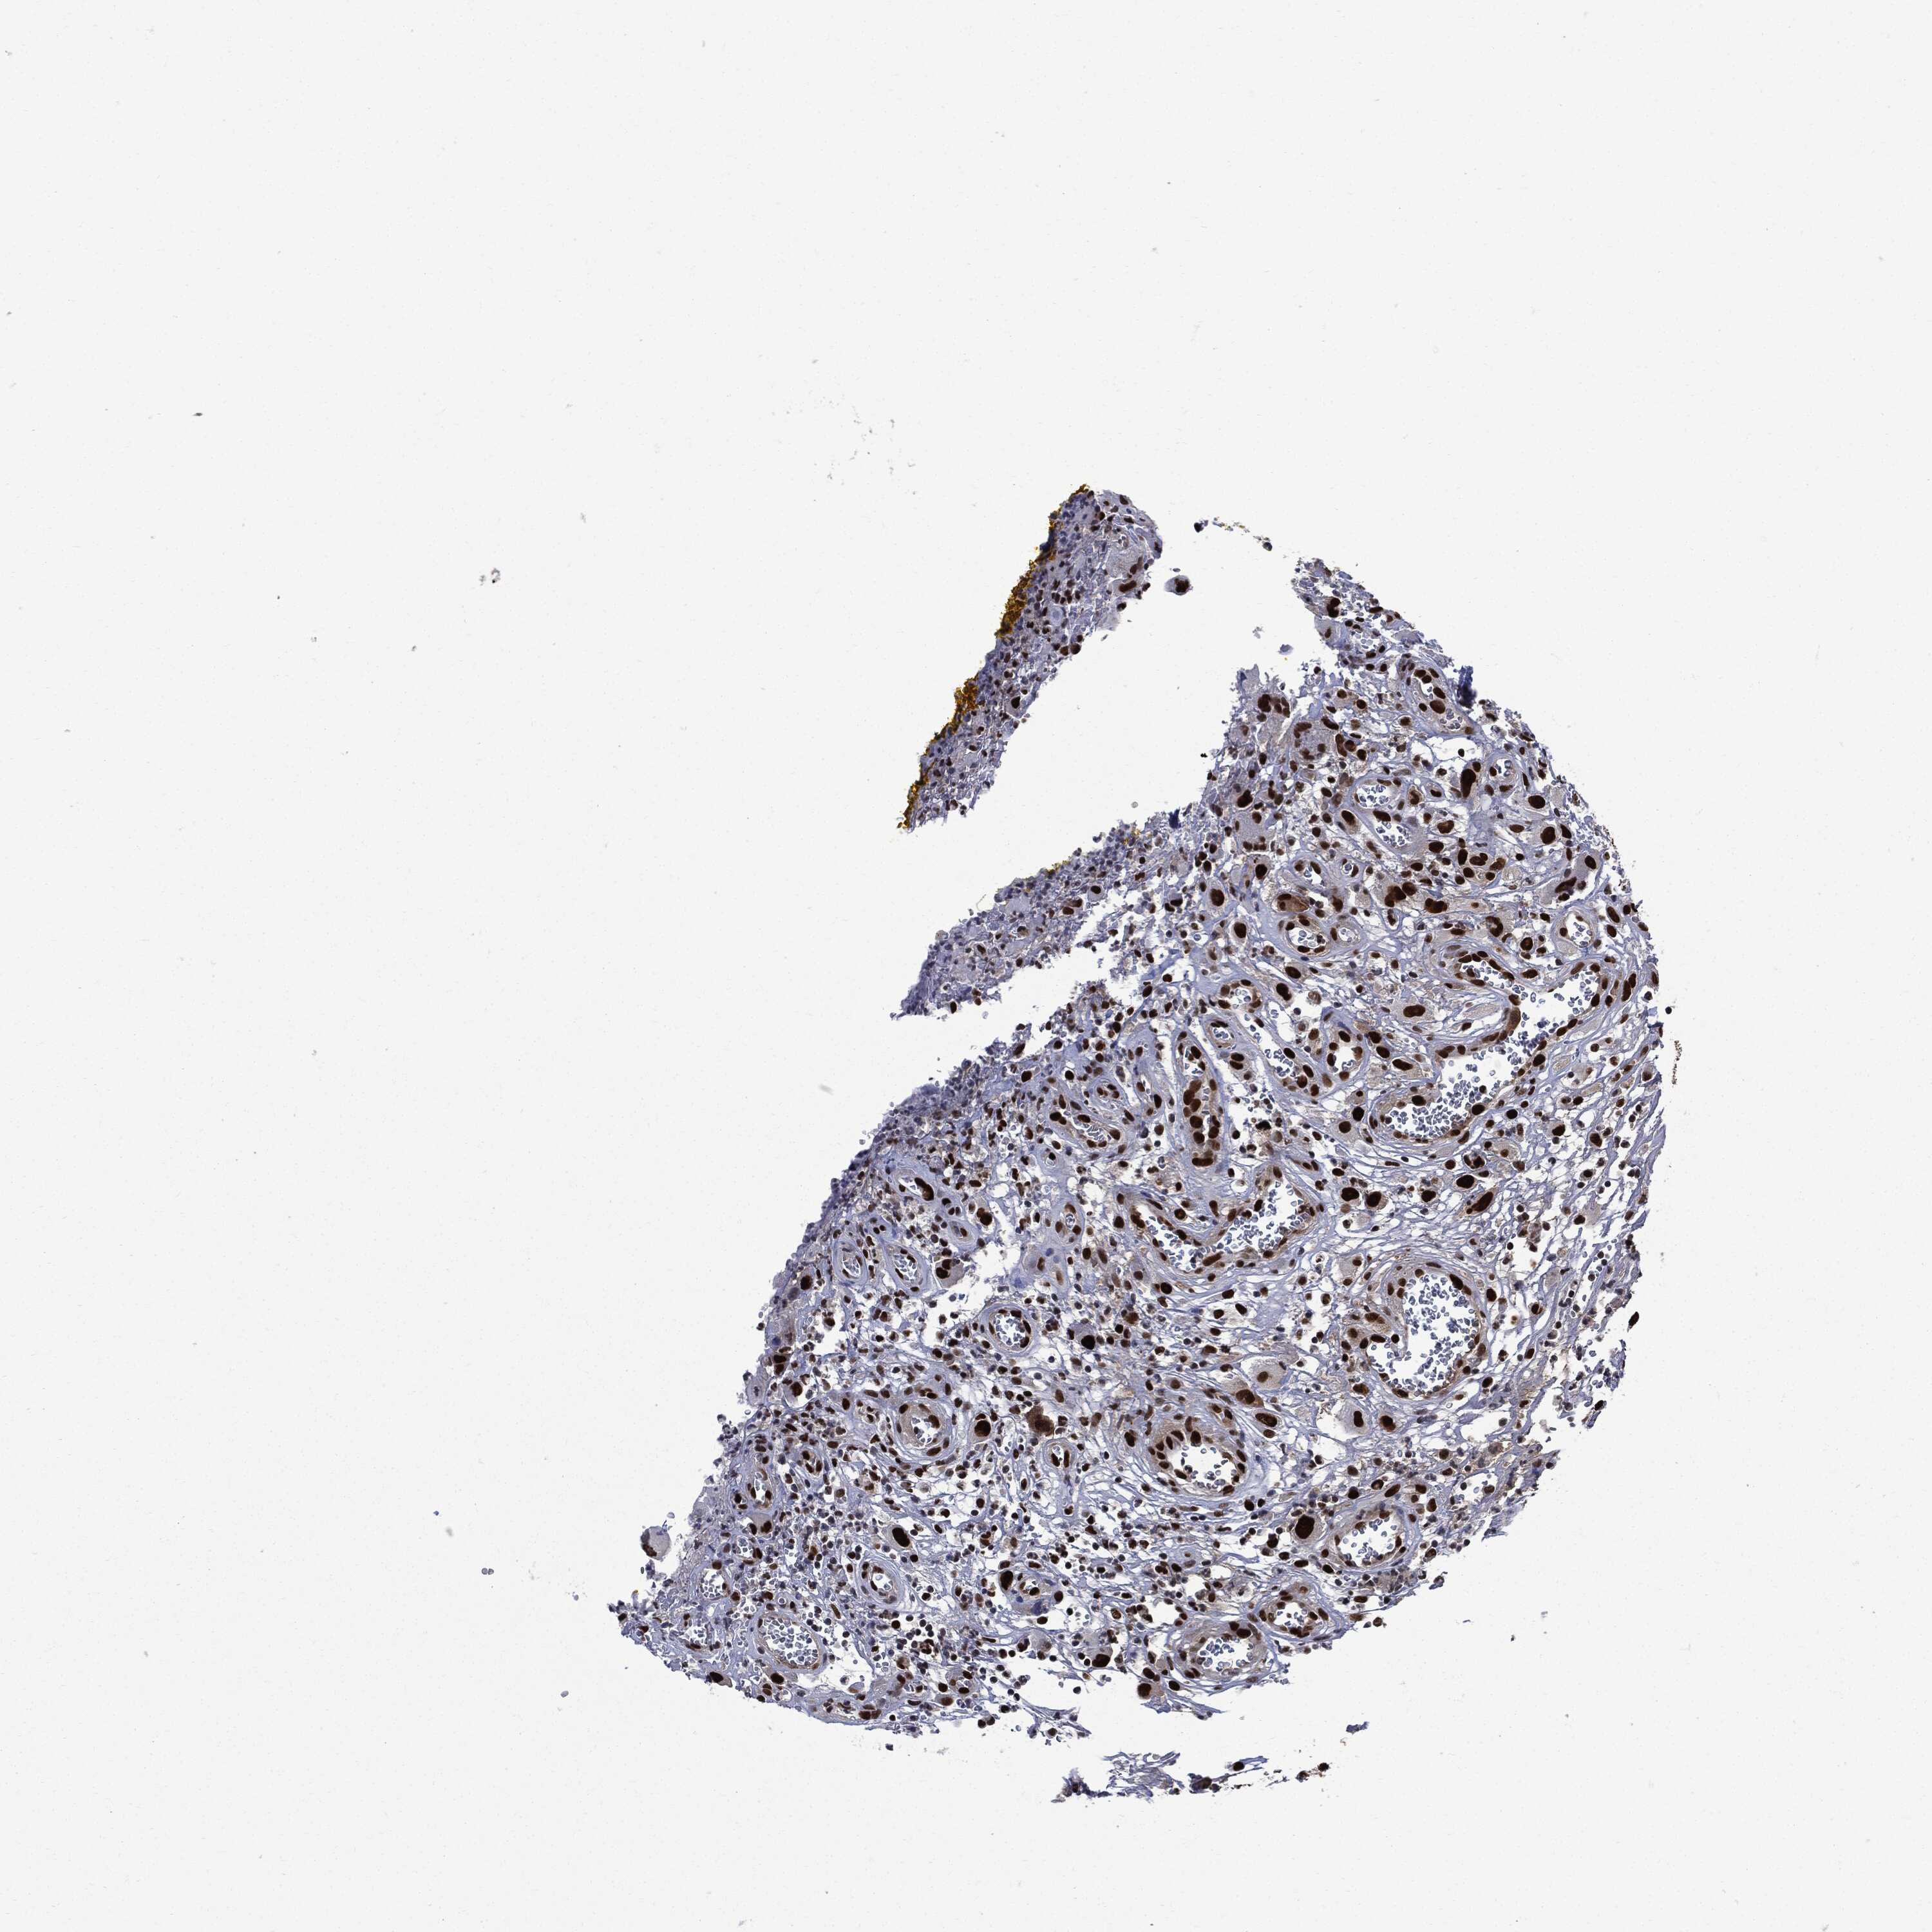

HEAD AND NECK CANCER - Protein expressioni

A mouse-over function shows sample information and annotation data. Click on an image to view it in a full screen mode. Samples can be filtered based on level of antibody staining by selecting one or several of the following categories: high, medium, low and not detected. The assay and annotation is described here.

Note that samples used for immunohistochemistry by the Human Protein Atlas do not correspond to samples in the TCGA dataset.

Antibody stainingi

Antibody staining in the annotated cell types in the current human tissue is reported as not detected, low, medium, or high, based on conventional immunohistochemistry profiling in selected tissues. This score is based on the combination of the staining intensity and fraction of stained cells.

Each image is clickable and will lead to virtual microscopy that enables deeper exploration of all samples and also displays staining intensity scores, fraction scores and subcellular localization as well as patient and tissue information for each sample.

HPA030521

HPA030522

HPA030523

CAB000148

CAB080240

CAB080241

CAB080242

Staining

High

Medium

Low

Not detected

Intensity

Strong

Moderate

Weak

Negative

Quantity

>75%

75%-25%

<25%

None

Location

Nuclear

Cytoplasmic/membranous

Cytoplasmic/membranous,nuclear

Squamous cell carcinoma, NOS

Squamous cell carcinoma, metastatic, NOS

Adenocarcinoma, NOS